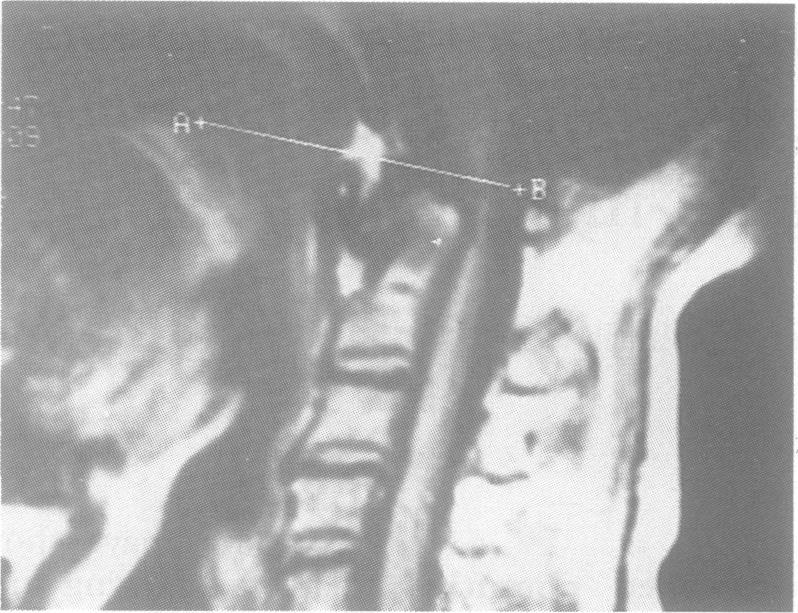

Clinical features and evoked potential recordings were analysed in 32 patients with congenital atlantoaxial dislocation before and after surgery. Seven patients (group 1) had atlantoaxial dislocation, while 22 patients had associated basilar invagination (group 2). In both groups, pyramidal tract signs, posterior column signs, wasting of the upper limbs, and abnormality of somatosensory evoked potentials (SSEP) were similar. Conversely, lower cranial nerve involvement and abnormal brainstem auditory evoked potentials (BAEP) were significantly more in patients with basilar invagination (p less than 0.05). All seven patients in group 1 and 17 patients in group 2 were operated upon. Clinical and electrophysiological deterioration were significant in patients with basilar invagination (group 2), following posterior fixation compared with group 1. Among the patients in group 2, who clinically deteriorated following posterior fixation, seven had transoral excision of odontoid and six of them improved both clinically and electrophysiologically. Two patients in group 2 had odontoid excision before posterior fixation, and in both the evoked potentials improved postoperatively. In group 1 the patient's BAEP remained unaffected following posterior fixation, however, in group 2, eight patients over 53% showed improvement in brainstem function following posterior fixation. This study shows the value of evoked potentials in congenital atlantoaxial dislocation, and rationalizes the surgical procedure in these patients. In patients with basilar invagination, odontoid excision is the preferred first stage procedure.

对32例先天性寰枢椎脱位患者手术前后的临床特征和诱发电位记录进行了分析。7例患者(第1组)有寰枢椎脱位,而22例患者伴有基底凹陷(第2组)。两组患者的锥体束征、后柱征、上肢肌肉萎缩和体感诱发电位(SSEP)异常情况相似。相反,基底凹陷患者的下颅神经受累和脑干听觉诱发电位(BAEP)异常明显更多(p小于0.05)。第1组的所有7例患者和第2组的17例患者接受了手术。与第1组相比,基底凹陷患者(第2组)后路固定后临床和电生理恶化明显。在第2组中,后路固定后临床恶化的患者中,7例行经口齿状突切除术,其中6例临床和电生理均有改善。第2组有2例患者在后路固定前进行了齿状突切除术,术后诱发电位均有改善。在第1组中,后路固定后患者的BAEP未受影响,然而,在第2组中,超过53%的8例患者后路固定后脑干功能有改善。本研究显示了诱发电位在先天性寰枢椎脱位中的价值,并使这些患者的手术程序合理化。对于基底凹陷患者,齿状突切除术是首选的第一阶段手术。